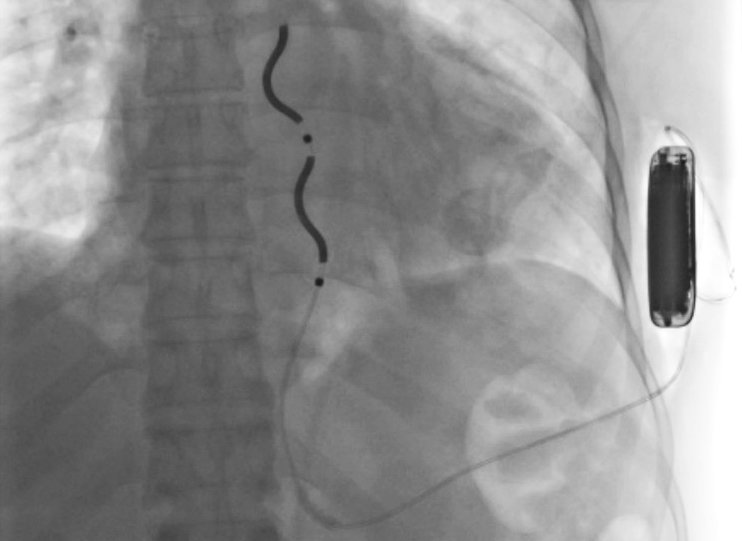

An implantable cardioverter defibrillator seen in this imaging scan

UVA Health was also among the first to implant the extravascular implantable cardioverter-defibrillator (EV-ICD), an ICD with leads outside of the blood vessels.